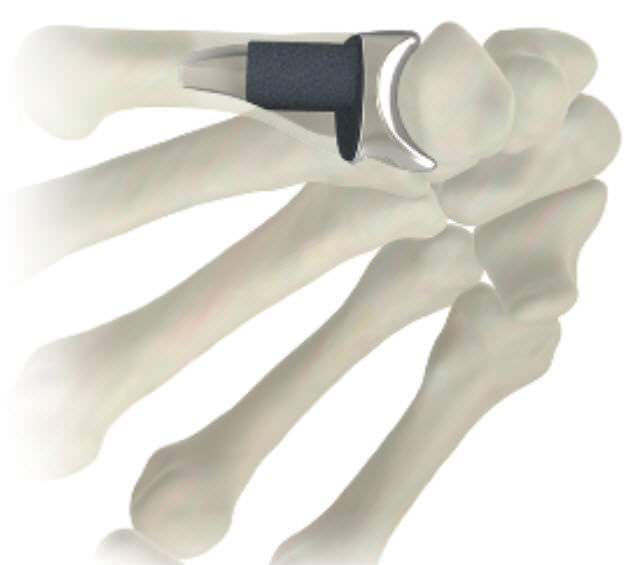

From www.medicalexpo.com

Metacarpophalangeal joint implant STABLYX ® Skeletal Dynamics What Is A Joint Implant  Makes an incision over the knee. Knee replacement surgery usually takes 1 to 2 hours. There are many orthopedic companies that produce different implants used in knee replacement. To perform the procedure, the surgeon: Thinking about a total knee replacement? The specific type of implant your surgeon uses will. During knee replacement surgery, an orthopaedic surgeon will resurface your damaged. What Is A Joint Implant.